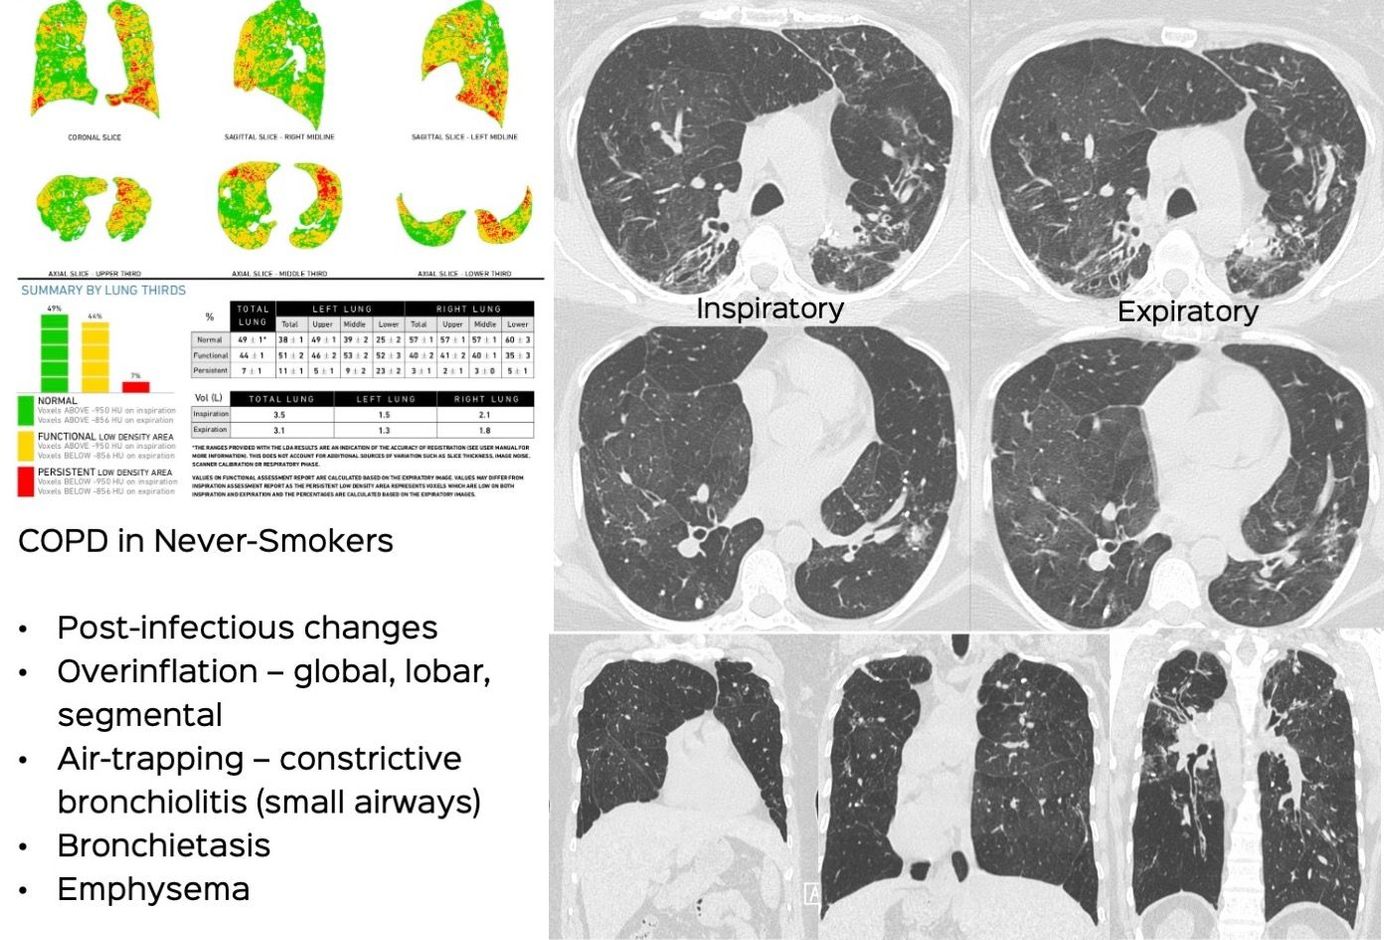

Case 54: COPD in a Never-Smoker Members Public

COPD can also occur in never-smokers, is common in India and the spectrum of findings should be recognized by radiologists

COPD